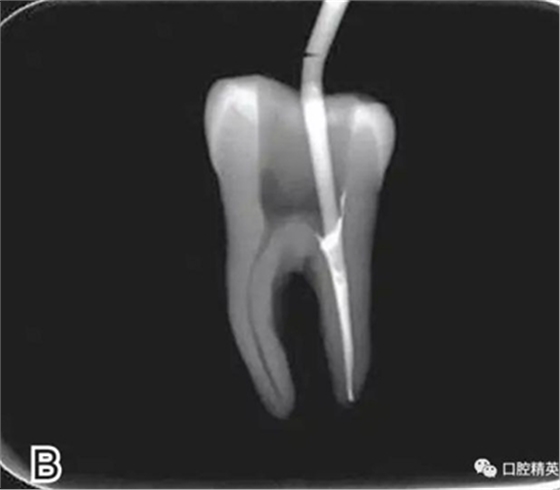

4、放置主尖及糊劑

將主尖的尖1/3 部分蘸一薄層根充糊劑,緩慢插入根管內(nèi),并左右旋轉(zhuǎn)主尖,以將根充糊劑均勻涂布于根管壁上,如圖4所示。

圖4 放置主尖及糊劑,A.放置主尖及糊劑 B.X線片下示主尖及糊劑的放置